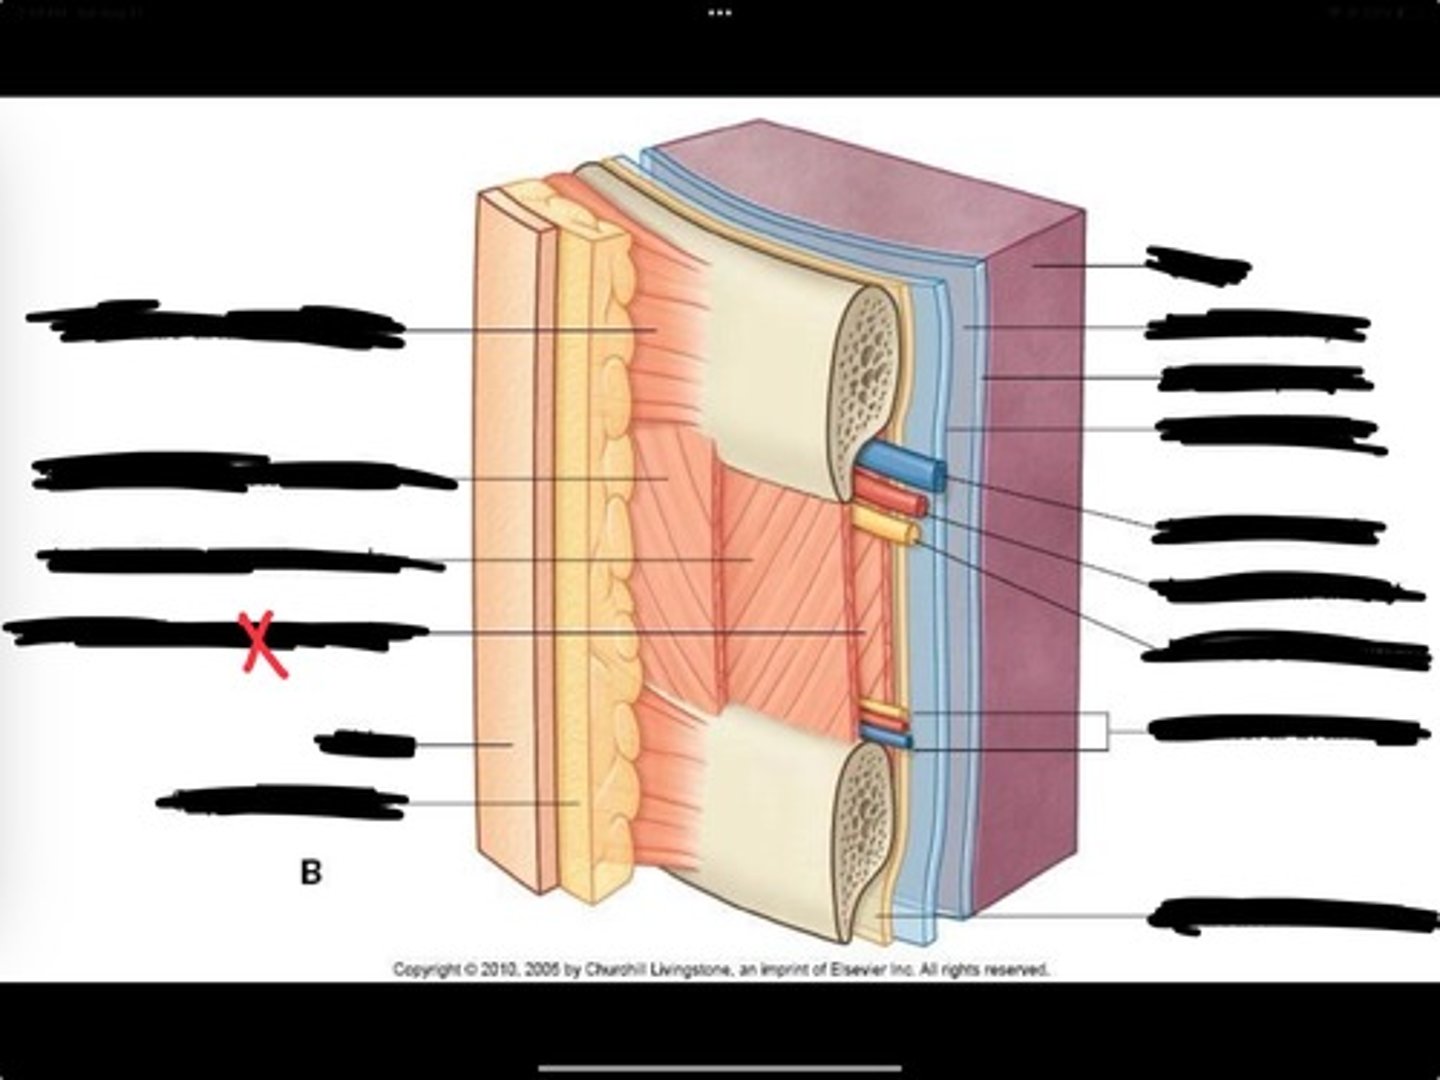

Innermost intercostal muscle

Skin

Inferior vena cava

Internal intercostal muscle

External intercostal muscle

Serratus anterior muscle

Lung

Pleural cavity

Visceral pleura

Parietal cavity

Intercostal vein

Intercostal artery

Collateral branches

Intercostal nerve

Endothoracic fascia